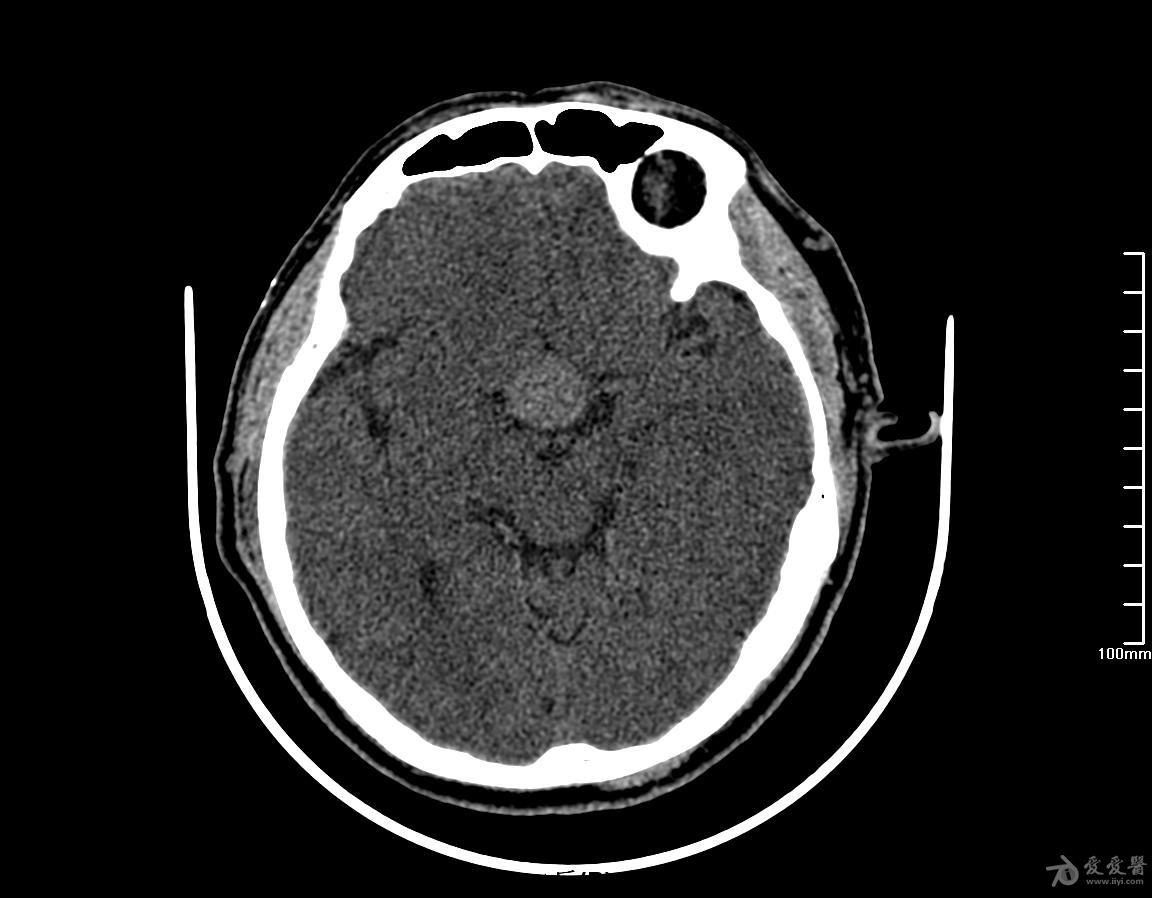

蝶鞍部占位穿刺术后复查